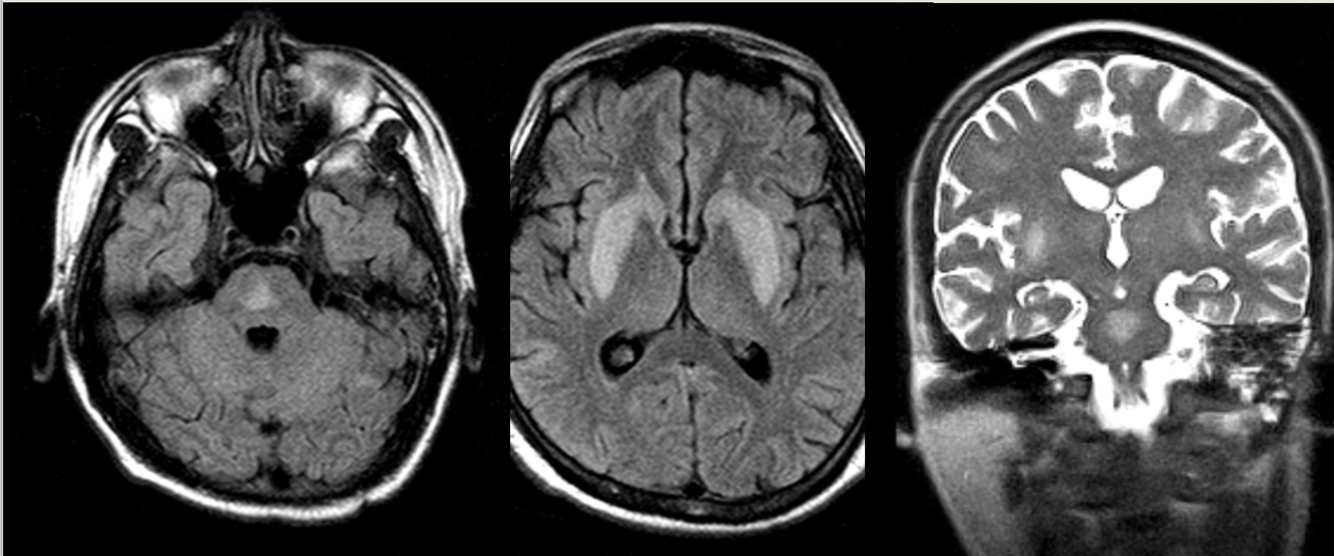

65 y/o M with rigidity.

Olivopontocerebellar atrophy